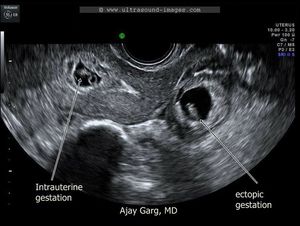

Heterotopic pregnancy in which both intrauterine pregnancy &extrauterine pregnancy (ectopic pregnancy)) are occure simultaneously...it occur in vitru fertilization(IVF)